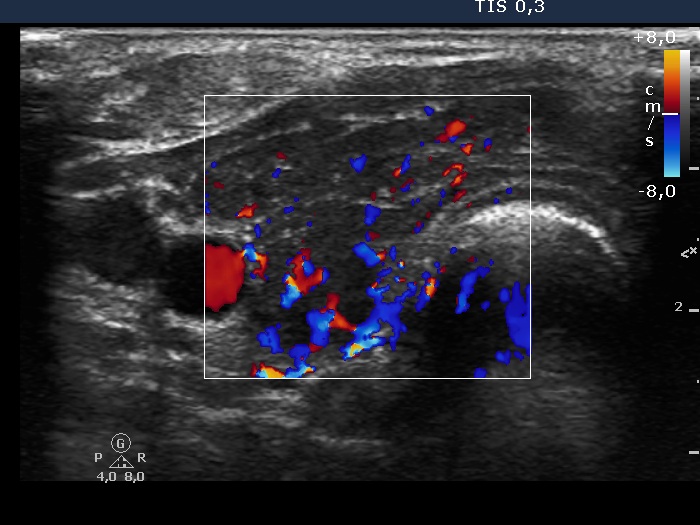

First examination (first and second rows of images):

Ultrasonography: A diffusely hypoechogenic thyroid was found with several discrete lesions. The vascularization was increased.